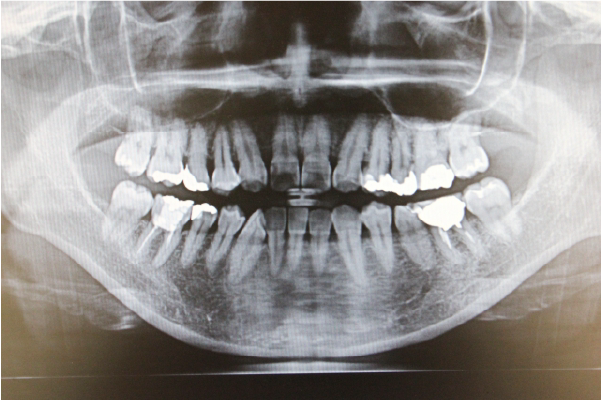

一般的な検査だけでなく、必要に応じてレントゲン検査を行うことで、骨や歯の根の状態まで正確に把握し適切に診断します。

レントゲン検査

必要に応じて

年1回程度

年に1回程度、骨の状態や、目には見えない虫歯や歯石の付着などを詳しく調べるため、レントゲン撮影を行います。